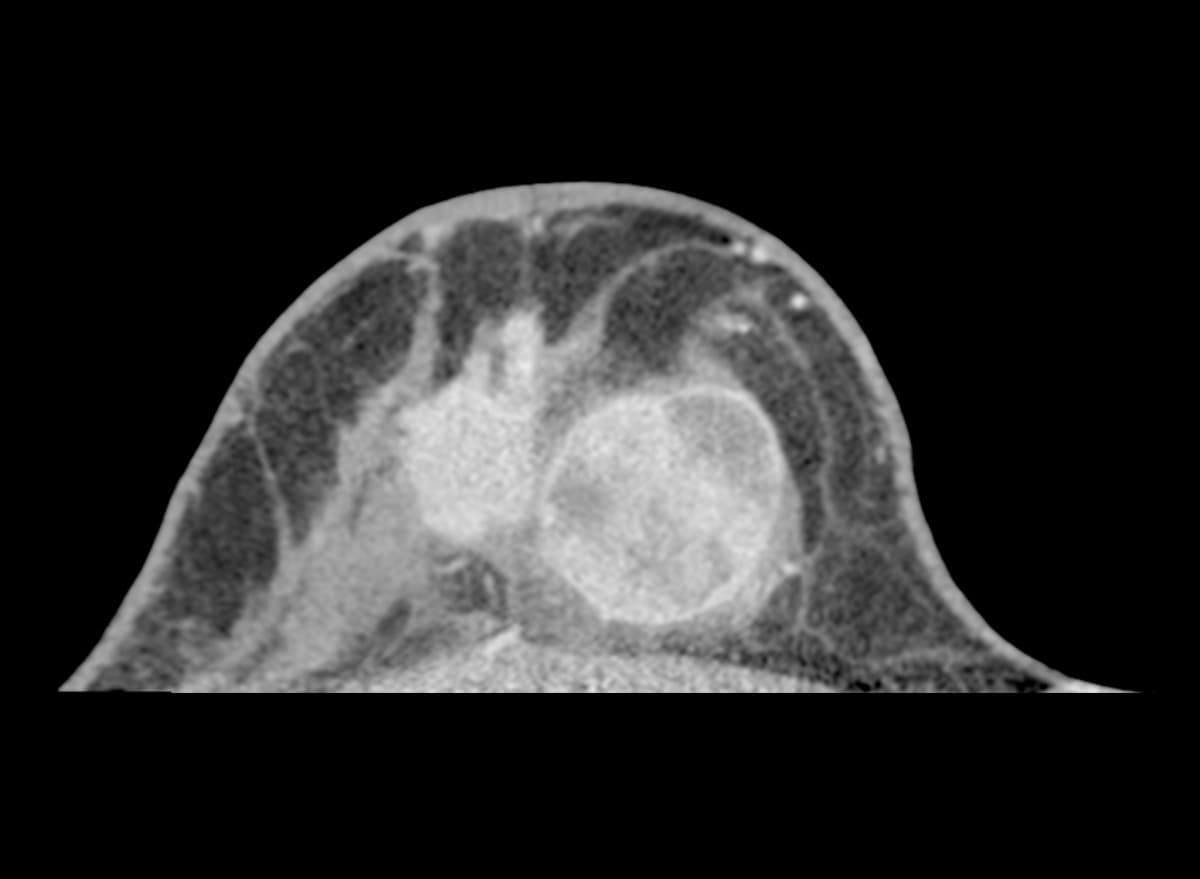

多発性乳がん

患者背景

• 70~79歳の女性で、右乳房に触知可能な腫瘤を認める。

• 過去のマンモグラフィでは単一の腫瘤のみが描出されていた。

• 超音波検査では、病変は円形かつ境界明瞭で、嚢胞性と固形成分を伴っていた。さらに、滑らかで不規則な辺縁を有する複数の低エコー性病変が検出された。

多発性乳がんの疑いを確認するため、乳腺CT検査を実施した。

画像詳細

• 造影前:円形の腫瘤性病変で、中心部に低吸収(壊死/液体)領域を認める。画像所見は複数の病変を疑わせる。

• 造影後:触知可能な腫瘤は造影剤を不均一に増強します。乳房の複数の象限に、不規則な縁と滑らかな縁を有する複数の造影増強腫瘤が明示されています。

評価:BI-RADS 5

画像提供:エヴリン・ヴェンケル医学博士(エルランゲン大学病院)